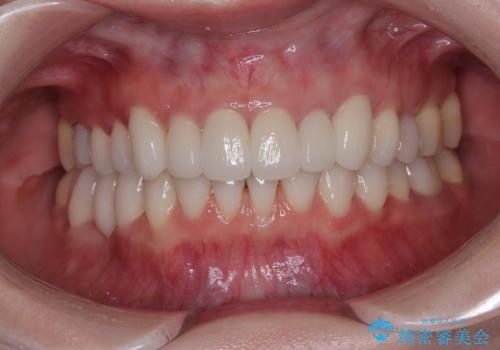

矯正治療自体はインビザラインで満足のいく仕上がりとなりました。

前歯は根管治療が必要となり、元々舌側に入り込んでいた左上2番目の歯は歯周外科処置により歯肉ラインを整えることとしました。

欠損部位は傾斜歯軸を起き上がらせることができたため、オールセラミッククブリッジにて補綴治療を行いました。

全顎的に満足のいく仕上がりとなりました。